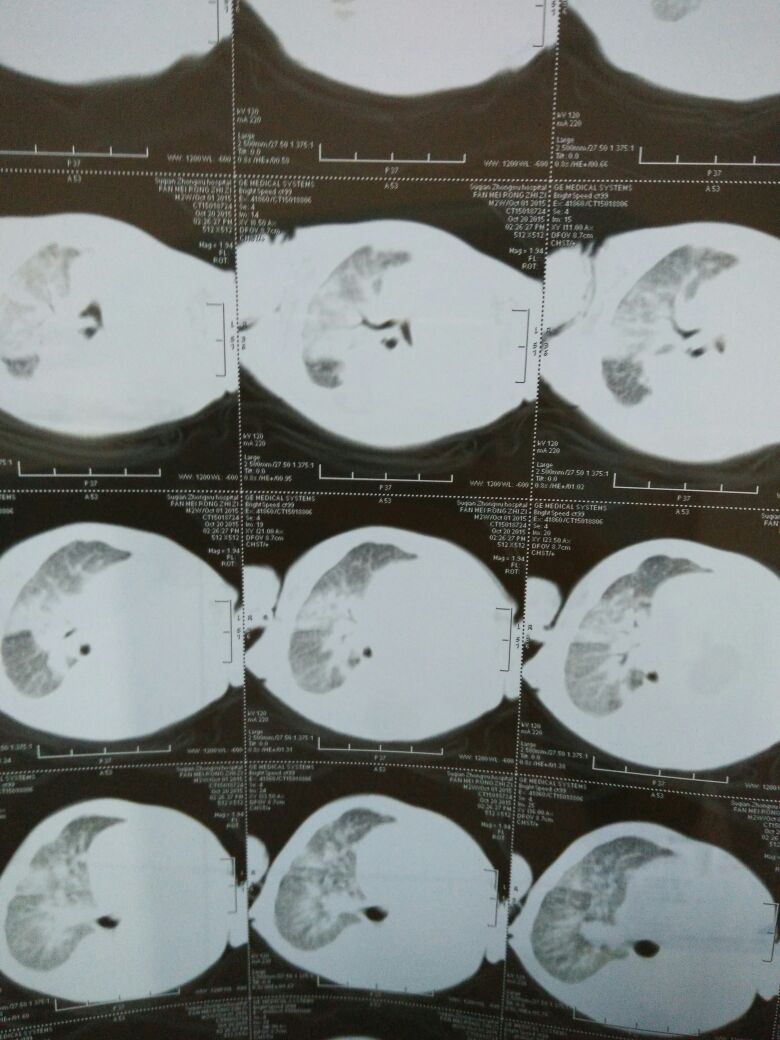

患者,女,27岁,于2013年9月9日入院。 主诉:间断头痛1年余,加重伴间断发热7个月。 现病史:2012年6月起无明显诱因出现头痛,两额角处疼痛明显,呈阵发性胀痛,无恶心、呕吐,体温正常,神志清楚,约半月至1个月左右疼痛1次,可自行缓解。2013年2月无明显诱因头痛加重,疼痛部位没变化,胀痛为主,伴有恶心、呕吐,未测体温,神志清楚。 2月12日至某县人民医院查头颅CT示侧脑室扩张,至某市医院就诊,体温40℃,腰穿颅压540mmH2O ,CSF白细胞20×10^6/L,单核98%,蛋白1.018g/L,糖0.3mmol/L,氯104mmol/L,ADA4U/L。CSF结核抗体(-),隐球菌抗体(-),诊断:结脑,转至某胸科医院,抗结核治疗、降颅压治疗,体温正常,间断测颅压200-300mmH2O,2个月后好转出院。 院外继续抗结核治疗,患者无明显不适,7月2日腰穿,颅压230mmH2O,CSF白细胞10×10^6/L ,蛋白1.69g/L,糖0.3mmol/L、氯118mmol/L、ADA2 U/L。8月中旬出现恶心,呕吐明显,体温正常,8月29日回至某胸科医院,腰穿颅压280mmH2O,CSF白细胞10×10^6/L ,蛋白2.88g/L,糖0.9mmol/L ,氯113mmol/L ,ADA3U/L。 既往史:1、无与诱发本病有关的基础病;2、无结核病接触史。 体格检查 1、体温正常,双肺、心脏、腹部、淋巴结无异常; 2、脑膜刺激征:颈部稍抵抗,克氏征、Brusinski征阴性。 辅助检查 1、血常规正常,血沉3mm/h,γ-干扰素A、B均为0.颈部超声未见异常。 2、9月11日颅压270mmH2O,CSF白细胞23×10^6/L ,单核99%,蛋白2.06g/L,糖1.13mmol/L ,氯107mmol/L ,ADA1U/L。隐球菌、结核检查阴性。CSF涂片细胞学:偶见淋巴细胞,未见肿瘤细胞。9月16日颅压280mmH2O,CSF白细胞9×10^6/L , 蛋白2.05g/L,糖2.2mmol/L ,氯108mmol/L ,ADA1U/L。 CSF涂片细胞学:偶见淋巴细胞,未见肿瘤细胞。 影像学检查: 头颅增强核磁:双侧脑半球脑质内可见多发指套状长T1、长T2信号,FLAIR序列病灶为高信号,颅底脑池狭窄,脑沟裂明显狭窄,诸脑室轻度扩张,中线结构未见明显移位。 增强扫描:沟裂池脑膜可见明显斑条状、结节状强化。